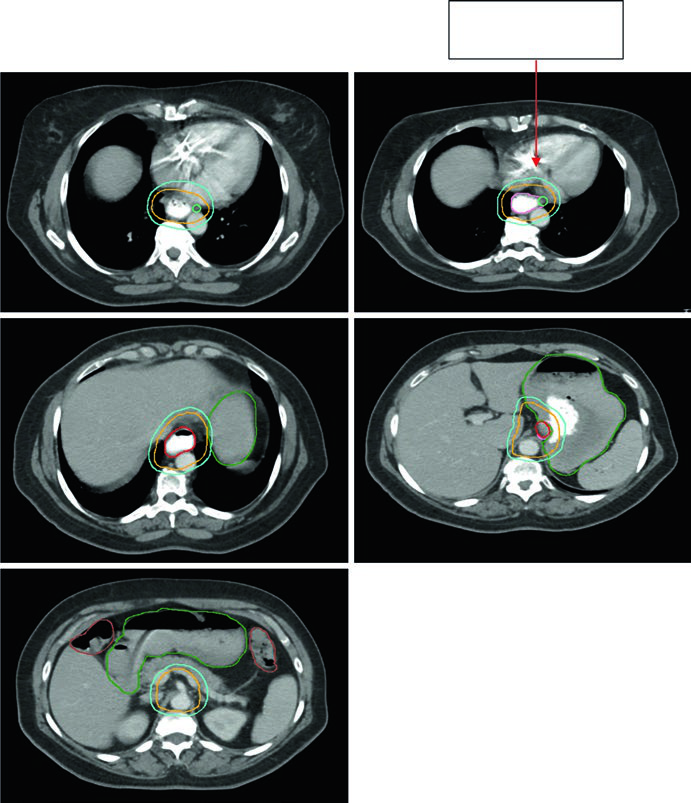

Case 4: GEJ Adenocarcinoma — 59-Year-Old, uT3N2

A 59-year-old patient with GEJ adenocarcinoma uT3N2. PET showed FDG-avid paraesophageal nodes and primary located 36–40 cm from the incisors. The sagittal planning CT shows the ITV reflecting GTV movement, with CTV covering 3–4 cm above the ITV. Volumes: stomach/duodenum (dark green), nodal GTV (light green), esophageal GTV (red), ITV (pink), CTV (orange), PTV 50.4 Gy (cyan). Paraesophageal lymph nodes were included in the treatment field.